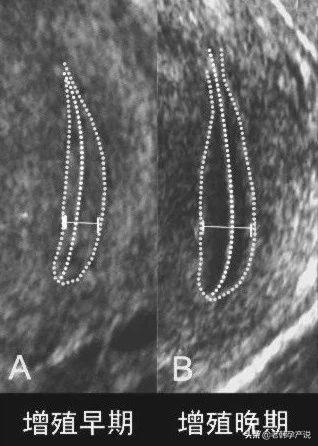

2.增殖期

月经周期的5-14天。这是内膜从“0”开始逐渐生长的过程,所以这个时期也是内膜最薄的时期,大约在0.5-1.0cm,超声检查可见明显的三线征

上图是优势卵泡直径达到18mm时子宫内膜的图像,呈明显三线征,中间的宫腔线回声强,上面的一条线以及下面一条线与宫腔线之间的组织呈低回声。

以上所说的形态都是在晚卵泡期,就是优势卵泡接近16-18mm(接近排卵前)所出现的征象。排卵后卵巢内形成黄体产生孕激素,使子宫内膜转化为强回声,所以内膜的息肉及回声不均匀就不容易观察了。所以观察子宫内膜的好坏最好在晚卵泡期,即月经周期第12天左右(假如月经周期是28天左右的患者)